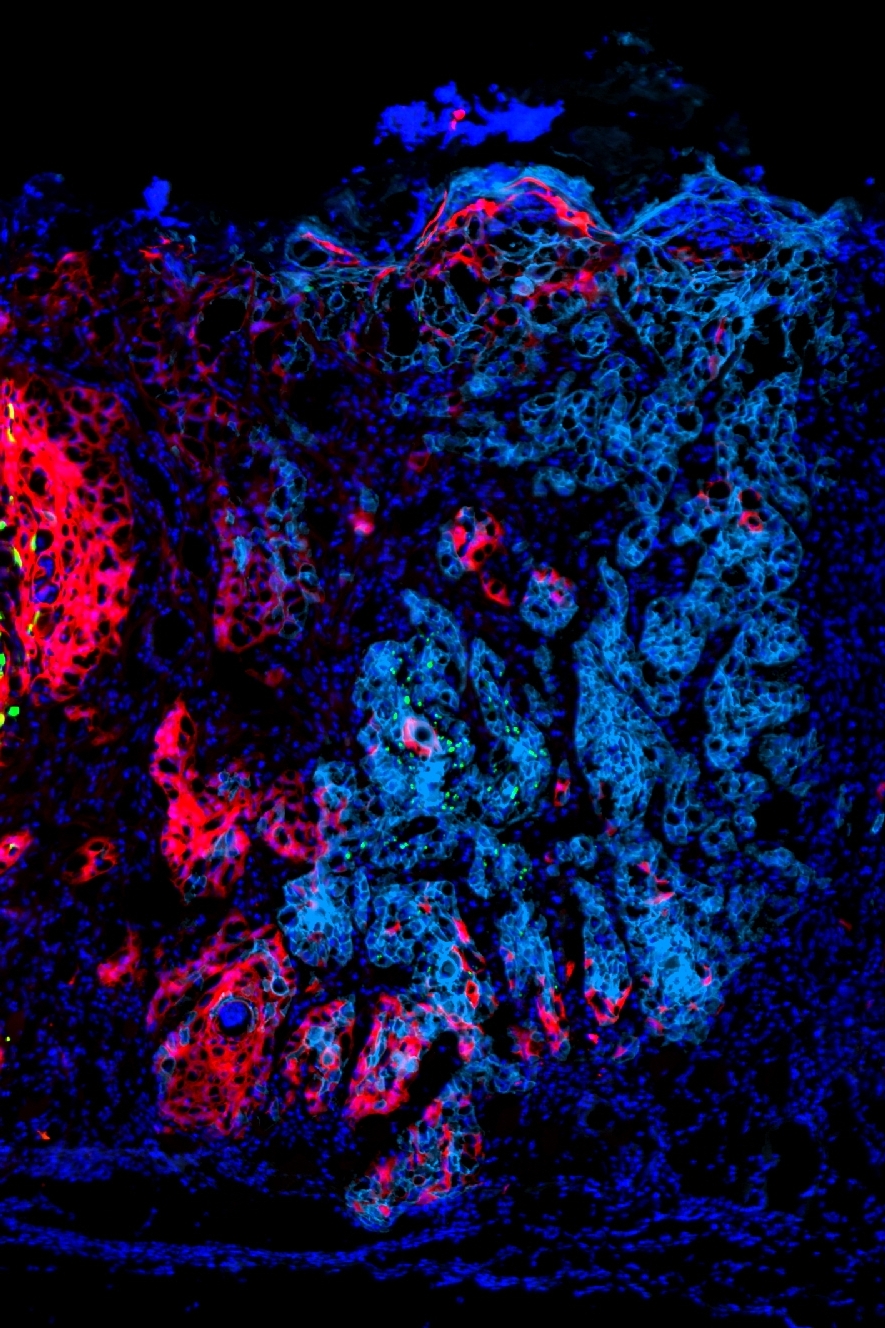

We have discovered that tumor cells drive the abundance and functional activity of immune cells on a highly localized spatial scale. We have established models of heterogeneous tumors comprised of either (1) an “immune hot” plus an “immune cold” tumor populations, or (2) two “immune hot” populations, and labeled the tumor populations with YFP (green) and RFP (red) fluorescent markers. In both cases, we find that the immune microenvironment adjacent to red versus green tumor cells is distinct, and T cell activity is unequal between tumor regions. Mechanistically, we find that “cold” tumor cells produce CX3CL1 to locally recruit macrophages and dampen T cell activity in their vicinity. We are currently investigating the effect of tumor-produced CX3CL1 on the tumor microenvironment, as well as identifying additional factors that tumor cells use to drive the spatial organization of immune cells within the tumor.